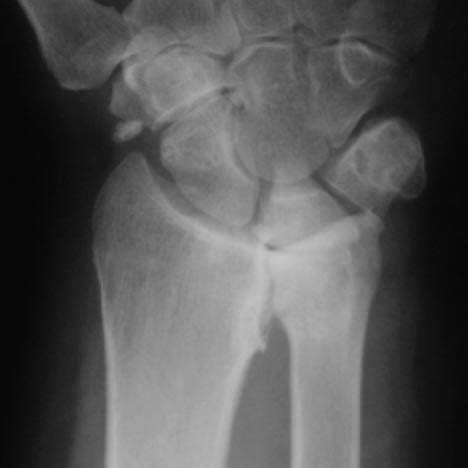

Patients who suffer from severe rotational instability of the forearm and pain in the Distal Radio-Ulnar Joint (DRUJ), may be able to attribute these symptoms to DRUJ fractures, ligamentous disruption or ulnar styloid fractures.

Recently, a new approach has emerged for treating DRUJ instability, arthritis of the distal ulna and traumatic injury – distal ulnar arthroplasty.

Expanded potential indications may include patients suffering from OA, rheumatoid arthritis, ulnar impaction with OA, failed Darrach procedures, failed matched resections, post-fracture management of the distal ulna and ulnar impaction without OA in patients who refuse to quit smoking.

This study used a prosthesis that was anatomically designed to replicate the distal ulnar head and its contact within the sigmoid fossa of the distal radius. The prosthesis has a cobaltchrome head and a titanium plasma sprayed stem. It may be applied with or without cement.